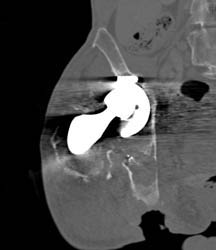

Non Union Femur Fracture